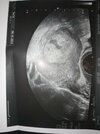

Cześć byłam dziś na wizycie u ginekologa wyszło że jestem jakoś w 5 tyg i 3 dni, lekarz zobaczył na USG taką jakby zatoczkę jest ona na pierwszym zdjęciu i przepisał mi duphaston bo uważa że to łożysko się zaczyna odklejać... Kazał się oszczędzać, będzie ciężko patrząc na to że mam dwuletnie dziecko w domu. Powiedziałam mu też że mam bóle podbrzusza. Wiem że nie jesteście lekarzami, ale na tym USG serio to tak wygląda ? Chodzi o tą jakby plamkę co jest pod tym całym łożyskiem, boje się że coś się stanie.

Nie mam żadnych plamien ani nic Poki co na szczęście bolą mnie tylko plecy na dole i to podbrzusze, robi się też twarde czasem ale myślę że to przez rozciąganie. A i po tym duphastonie zaczęło mnie boleć właśnie to podbrzusze jakby bardziej..

znaczy po prostu nie będę go brała na ręce, tak to nie jest mały aż taki zły haha dokucza trochę. Właśnie myślę czy mi dał to przez tą plamę czy przez to że mu powiedziałam że mnie boli podbrzusze trochę, ale on spojrzał na USG i powiedział że to wygląda tak jakby groziło poronienie właśnie przez tą plamkę...

szczerze mówiąc to już sama nie rozumiem... Mówił po prostu że ciąża moze się nie utrzymać bo to wygląda jakby się odklejało...